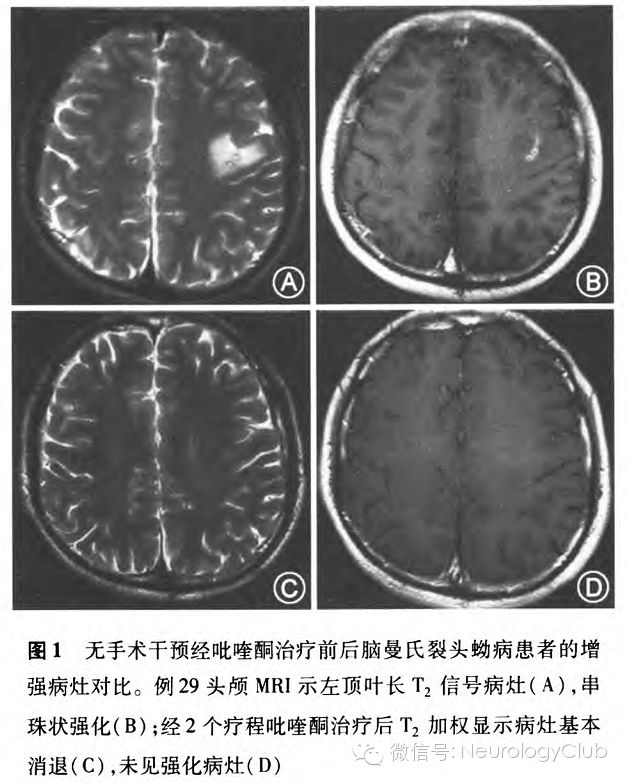

在长期随访(随访时间点为4个月、6个月、12个月、34个月和96个月)中均无患者失访,未行手术治疗仅口服吡喹酮治疗的患者18例预后良好,治疗前影像学检查T2WI呈长T2信号,中间混杂信号(图1A),增强后呈串珠状强化(图1B),大剂量吡喹酮给药后复查影像学T2WI病灶基本消退(图1C),强化病灶消失(图1D),消失时间分别为治疗后4个月(3例)、6个月(9例)、12个月(3例)、16个月(1例)、34个月(2例)。在随访期间,1例原左顶叶病变开颅手术患者未取到活虫,于术后6个月影像学复查示右侧小脑半球出现新的病灶。38例患者基本达到临床痊愈,4例残留不同程度的肢体瘫痪。9例患者存在不同程度癫痫发作,需长期服用抗癫痫药物,其中1例经吡喹酮治疗痊愈患者在96个月时再发抽搐,影像学随访为双顶叶软化萎缩。

所有患者均接受至少2次MRI扫描(在诊断时和治疗后)。42例患者中单侧强化孤立病灶者41例,占97.6%(41/42),双侧强化病灶者l例,占2.4%(1/42)。幕上病灶40例,占95.2%(40/42),幕下病灶2例,占4.8%(2/42)。病灶主要以额顶叶为主,占69.0%(29/42)。头颅MRI病灶表现为T1加权像低信号(图2B),T2加权像高信号,部分患者可见点状的混杂信号(图2C)。增强MRI显示38例患者病灶呈聚集的多发小环状强化,典型者表现为绳结状(图2D);14例患者病灶呈隧道样强化,特别在矢状位和冠状位明显(图2E),隧道一般长l-5cm,宽0.3-1.2cm,T1加权像为低信号、稍高信号或等信号,T2加权像为高信号。此外,随访MRI发现13例患者存在新旧病灶迁移(图2F),从额顶到顶枕5例;从额顶到颞叶3例;从顶叶到小脑半球2例;从左额叶到右额叶再到枕叶l例;从脑干到丘脑到顶叶1例;从基底节到额顶到胼胝体1例。